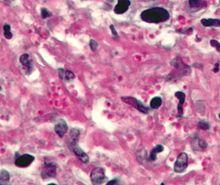

Haematoxylin and eosin (H&E) staining

Haematoxylin and eosin staining is frequently used in histology to examine thin tissue sections.[10] Haematoxylin stains cell nuclei blue, while eosin stains cytoplasm, connective tissue and other extracellular substances pink or red.[10] Eosin is strongly absorbed by red blood cells, colouring them bright red. In a skillfully made H&E preparation the red blood cells are almost orange, and collagen and cytoplasm (especially muscle) acquire different shades of pink.